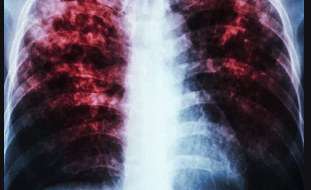

[263Chat] The government has committed to ending Tuberculosis (TB) in line with the United Nations declaration to end the deadly disease by 2030.